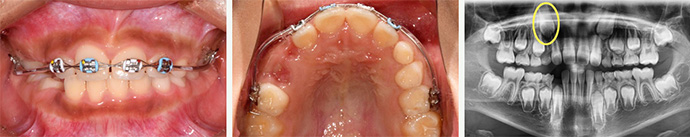

본원에서 진료받은 동일 환자분의 사진으로 치료 전 2014년 6월 21일~치료 후 2016년 1월 16일 동일 조건하에 촬영하였습니다.

7세 아이의 앞니가 거꾸로 물려있는 경우로, 진단 결과

골격적인 문제가 아닌 치아가 원인인 기능적 Ⅲ급 부정교합입니다.

들어간 앞니를 앞으로 밀어주는 핑거스프링이 포함된 가철성 장치를 장착해 교정합니다.

3개월만에 위아래 치아 맞물림이 정상화되었으나

상악 측절치가 영구치인 송곳니의 맹출 경로를 막고 있어

영구치가 제대로 자리를 잡도록 치근 경사를 조절하기 위해

브라켓을 부착합니다.

측절치 치근 이동으로 송곳니의 맹출방향이

제대로 변경된 것을 확인하고 치료를 종료합니다.